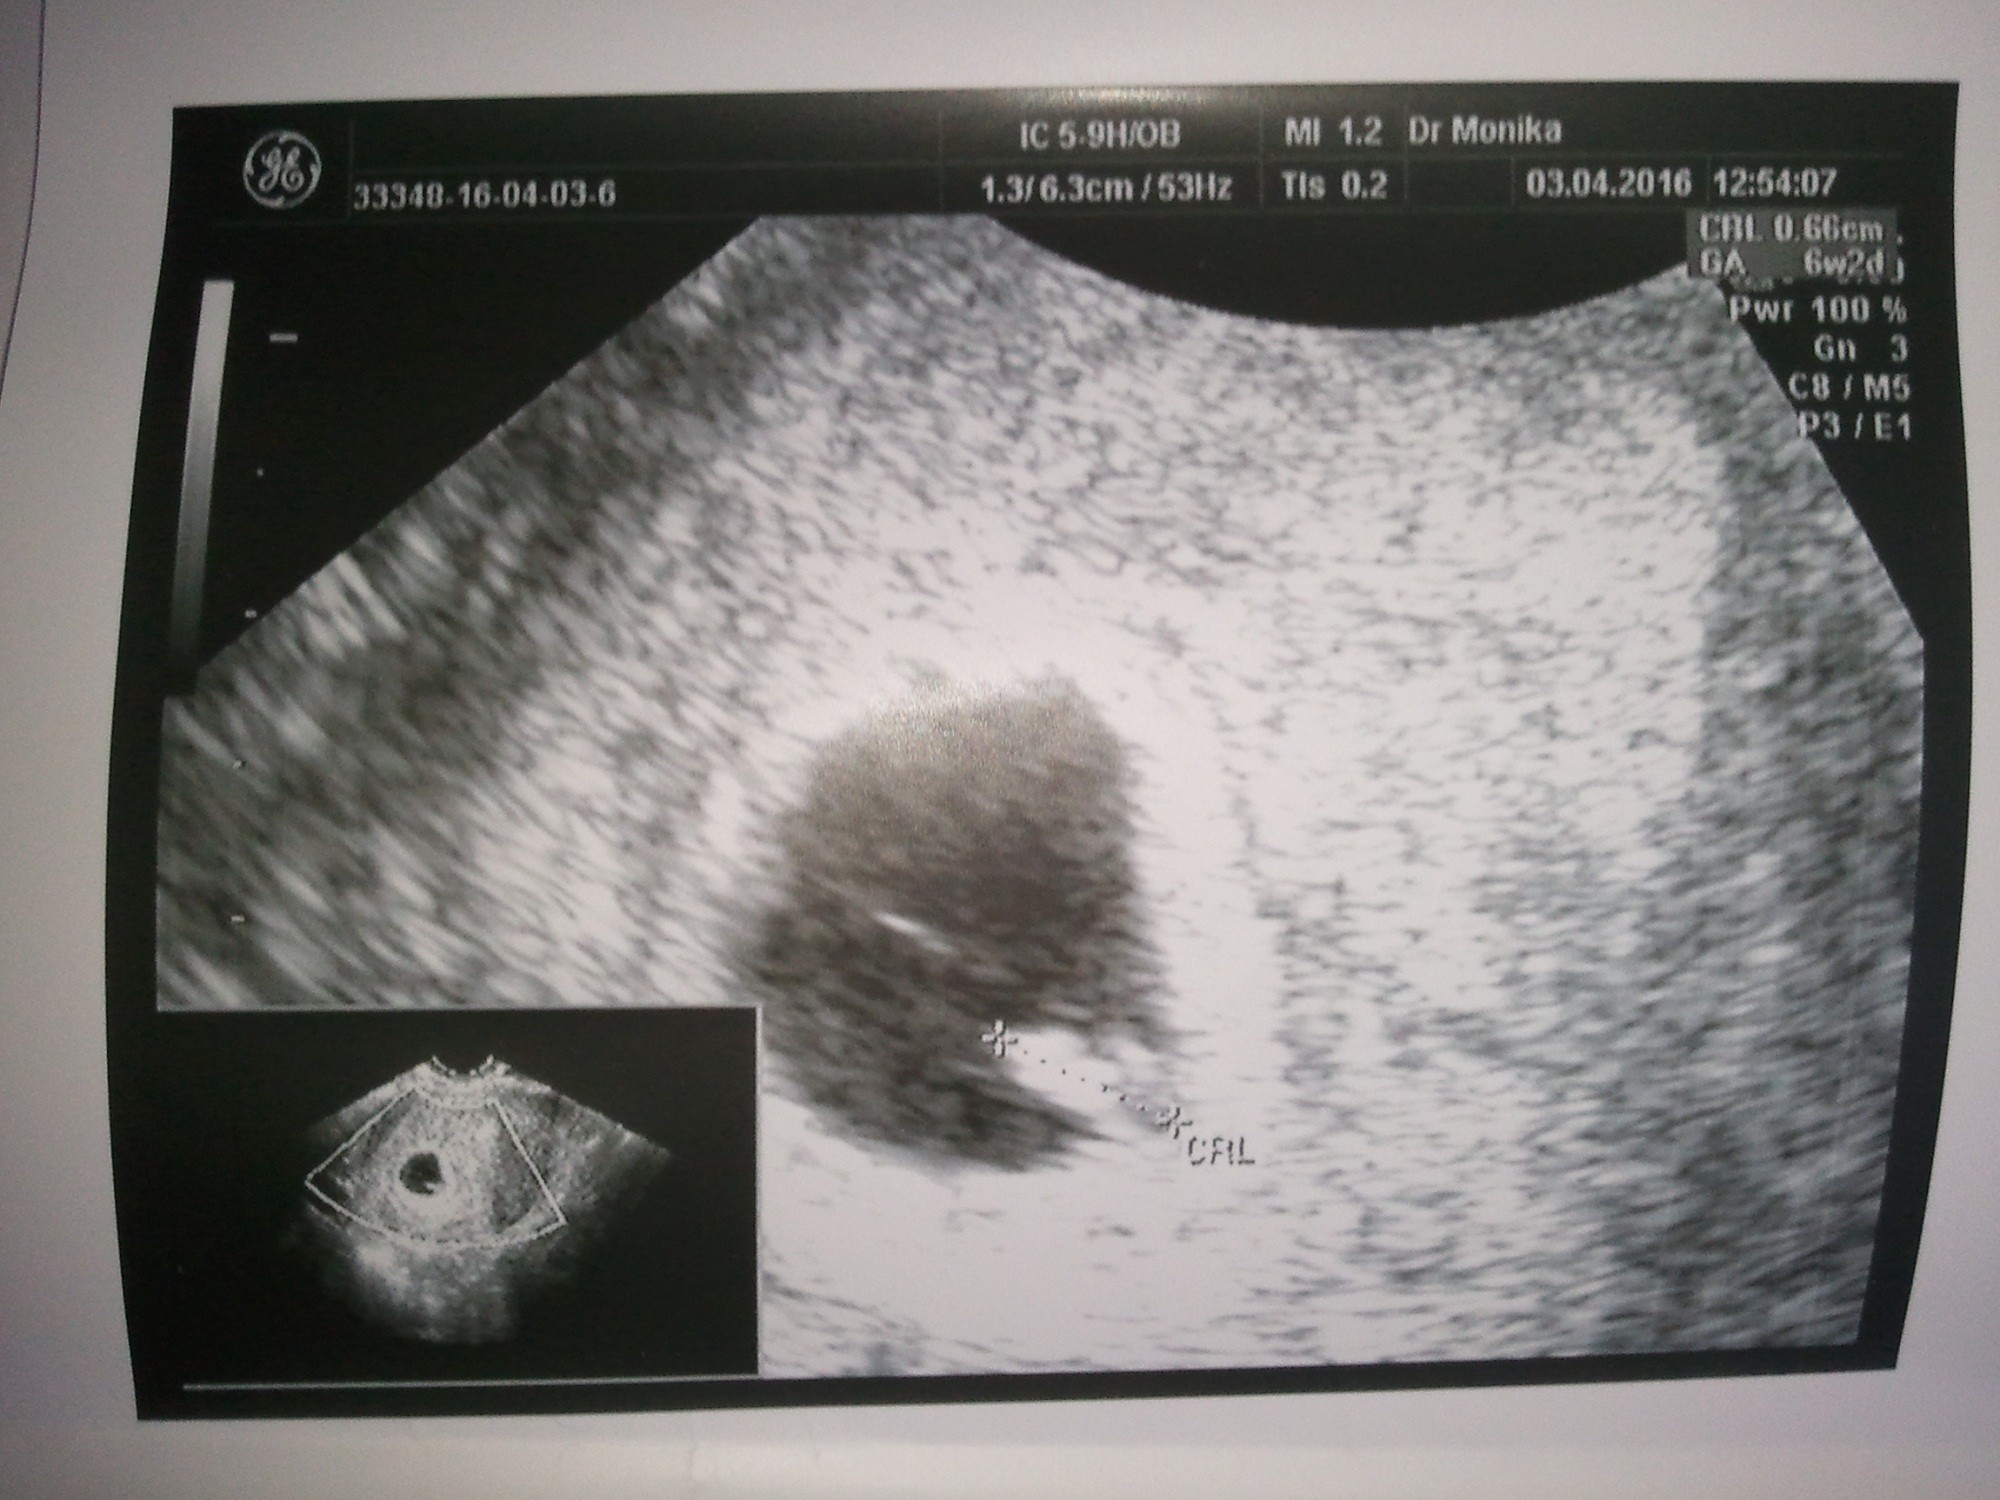

jeden dzień wyprzedził Om :D, wczoraj było wg om 6t1d, a wg usg 6t2d . Mam fotę i to nawet kilka :D

Załączniki

• 20160404_075608.jpg

20160404_075608.jpg

526,1 KB · Wyświetleń: 105

tęczowa super! Bardzo się cieszę, że maluszek tak ładnie się rozwija. :happy: Świetne zdjęcie.